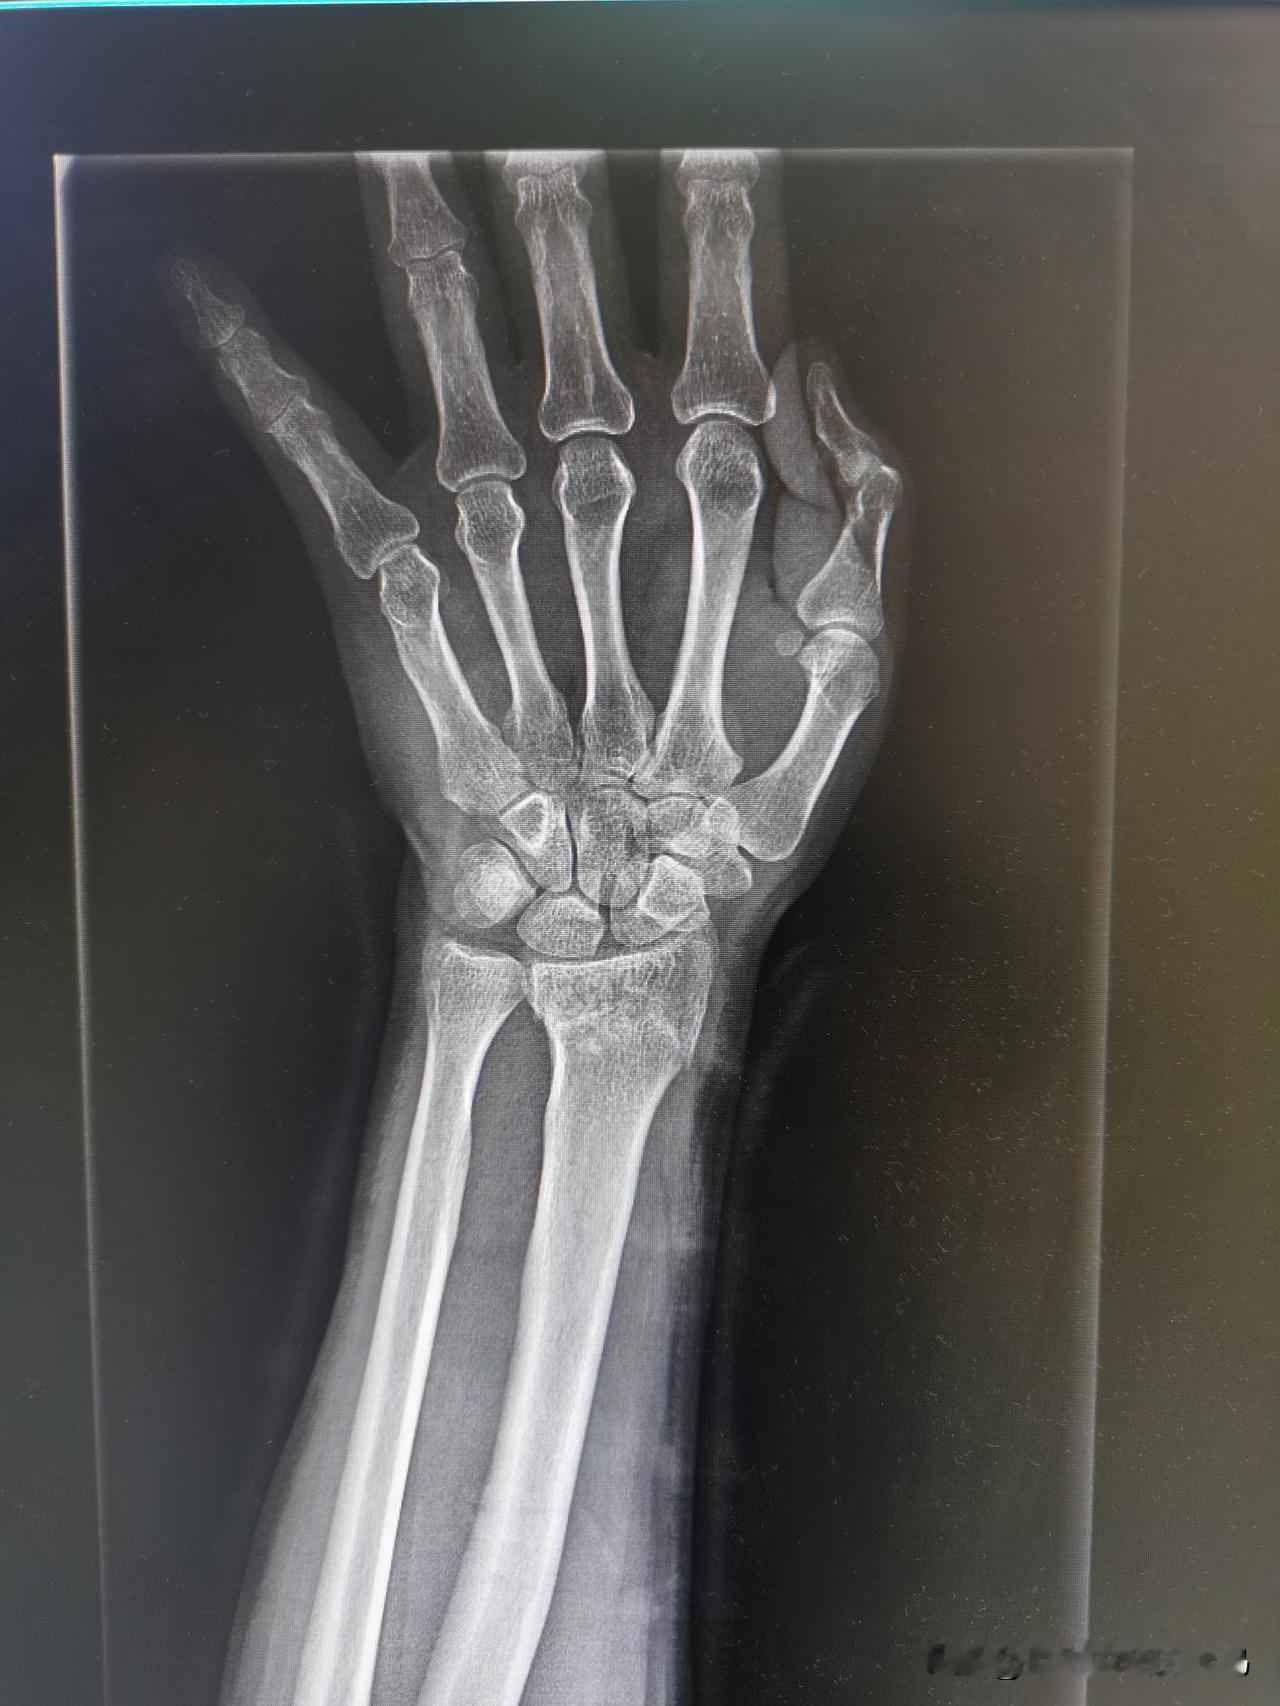

到底西医刀到病除,还是中医妙手回春? 霉气都是自找的! 节前最后一天,大晴天,已经连续下了大半个月的雨,从10月1日开始再下半个月,气温直接干到个位数。所以想抓住为数不多的晴天,晒晒太阳,修复心情。 沿着河边走路,沐浴着阳光,欣赏着秋景,一切都是那样的自然。 好奇害死猫。男人对钓鱼根本无免疫力,看到桥下有钓友中鱼,兴冲冲跑过去,忽略了半坡的湿泥,直接一滑,左手本能撑地。 悲剧来了,钻心的疼,两鬓豆大的汗珠,在朋友的帮助下坐在旁边缓缓,止不住的疼,还有湿透的后背。朋友拉着我去医院拍片检查,看看有没有骨折。 还好最近的医院就是宇宙第一大医院的东院区,挂了急诊去拍片。内心希望是挫伤,最坏的是骨折,现实生活中往往就是最坏的结果,确认骨折!附图一。 急诊医生把片子发给主治医生等治疗方案,等了一会主治医生过来了,直接说必须住院手术!先消除瘀血肿胀,等几天手术打入钢钉!整个假期全完了! 问问能否正骨复位,得到的是西医只会手术,不会正骨。没办法,我把结果拍下来发给一个中医老兄,询问这种情况是不是必须要手术。 否极泰来,峰回路转。得到老兄可以正骨复位的治疗方案,心情好了很多。赶去老兄给联系的郑州骨科医院,节前的堵车很疯狂,10多公里的高架桥硬是走了一个半小时。 到了骨科医院 检查确认就安排复位操作,两个医生一人一个方向,拉扯,按摩,摔倒的时候有多疼,复位的时候有多痛,能量守恒定律。 又去拍片看复位的结果,对位对线比较理想,不用手术,得到了最满意的结果,图片二。 夹板固定,打上石膏,拿了点促进骨骼生长的药,回家静养,等候复查。 疼的睡不着,自己变成了《无间道1》中梁朝伟扮演的陈永仁,学着他发摩斯密码,苦中作乐吧。 思考一个问题,到底西医刀到病除,还是中医妙手回春? 为什么对西医的治疗方案天然排斥? 为什么对中医保守治疗更为倾向? 欢迎大家在评论区发表自己的意见。